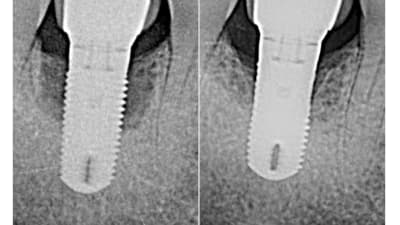

Case Series Implantology Implant Placement Lateral to the Inferior Alveolar Nerve: Selective Indications and Treatment Outcomes—A Case Series By Georges Tawil, DDS, Peter Tawil, DDSDDS, Ziad Salameh, DDS September 01, 2022 21 min read